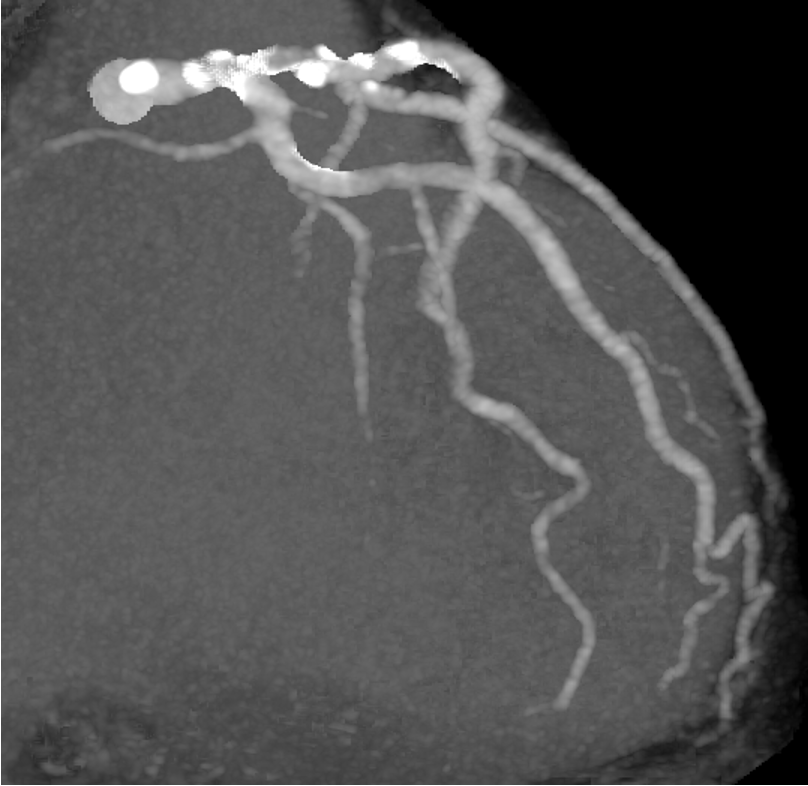

LCA CAG

-

15:20 - 16:50 Live Demonstration 4